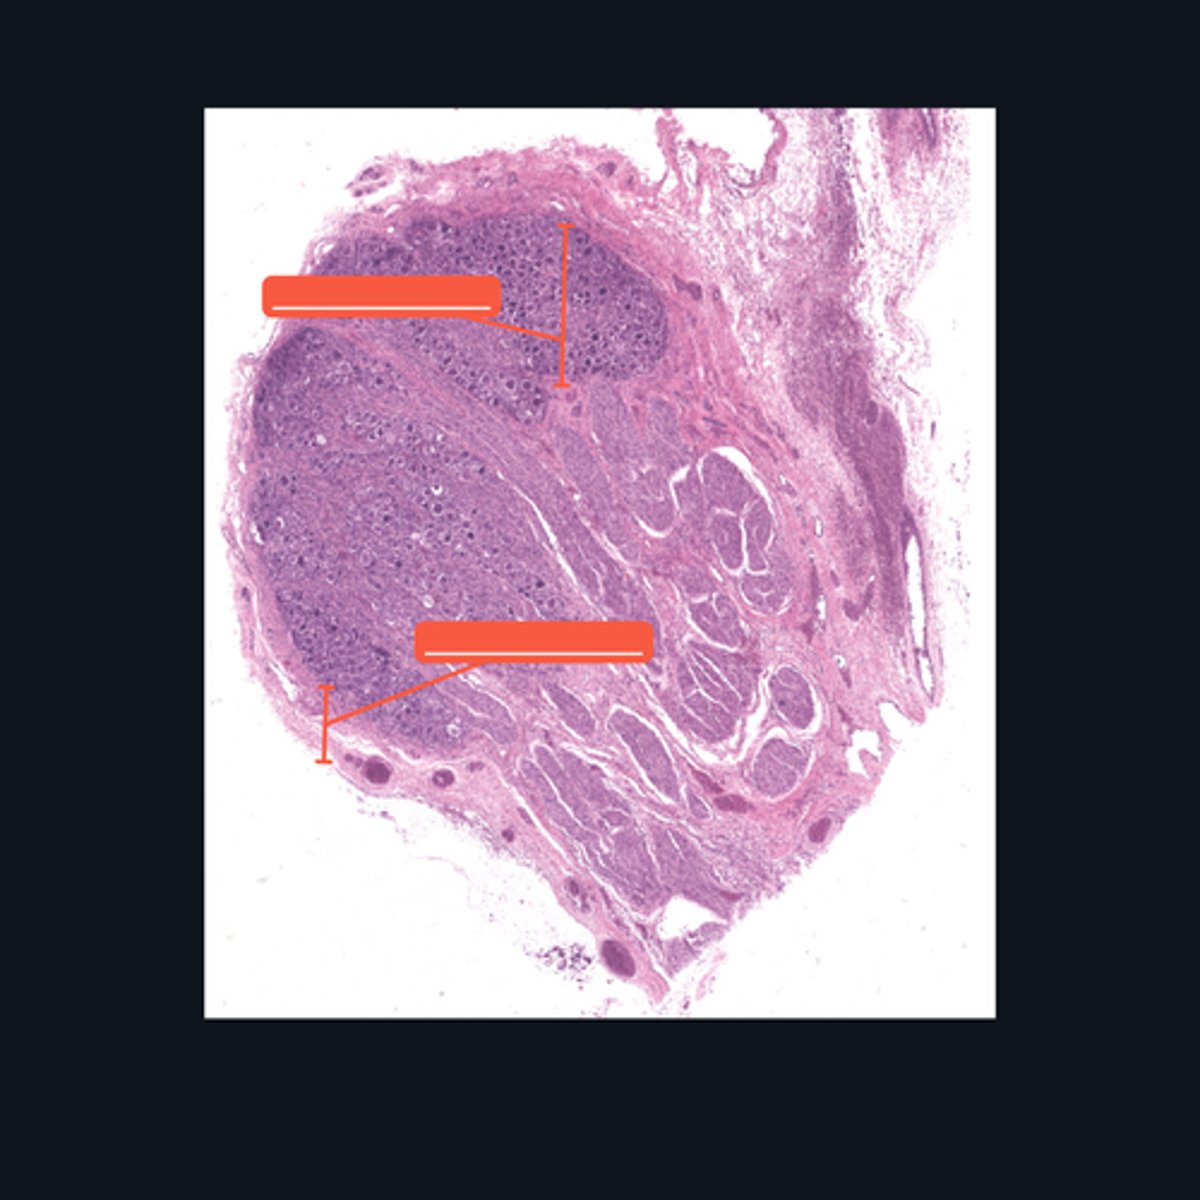

Dorsal root ganglion and nervous tissue

Identify the specific structure given in the image, as well as the type of tissue predominating in the structure.

(top to bottom)

Somatic sensory neurons

Capsule

Identify the structures of the dorsal root ganglion. Be as specific as possible.

(top to bottom)

Cell body

Satellite cell

Nucleus

Nucleolus

Nerve fibers

Identify the parts of the spinal ganglion in high magnification.

False, pseudounipolar

T or F: The neurons that congregate in this structure is multipolar.

(bottom to top)

Capsule

Ganglion Cell

Satellite cell

Nerve fibers

Nucleolus

Nucleus

Nissl Granules

Identify the structures of a sympathetic ganglion.

Multipolar, autonomic motor neurons

What kind of motor neurons are present in this structure?

Dense Irregular Connective Tissue

What kind of tissue is the capsule of a spinal ganglion made up of? Be specific.